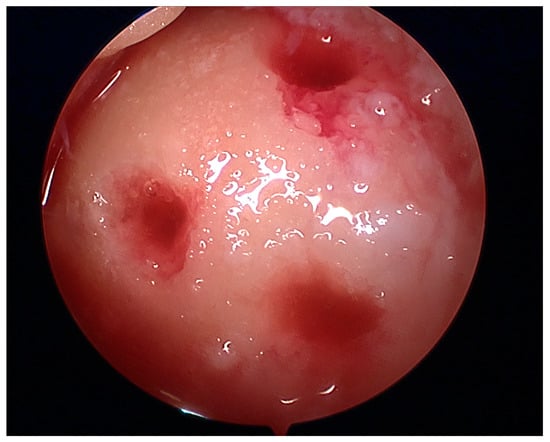

Figure 5.

Arthroscopic view of grade III lesion with a visible cartilage deficit of less than 50% (arrow) in the femoral trochlear groove.